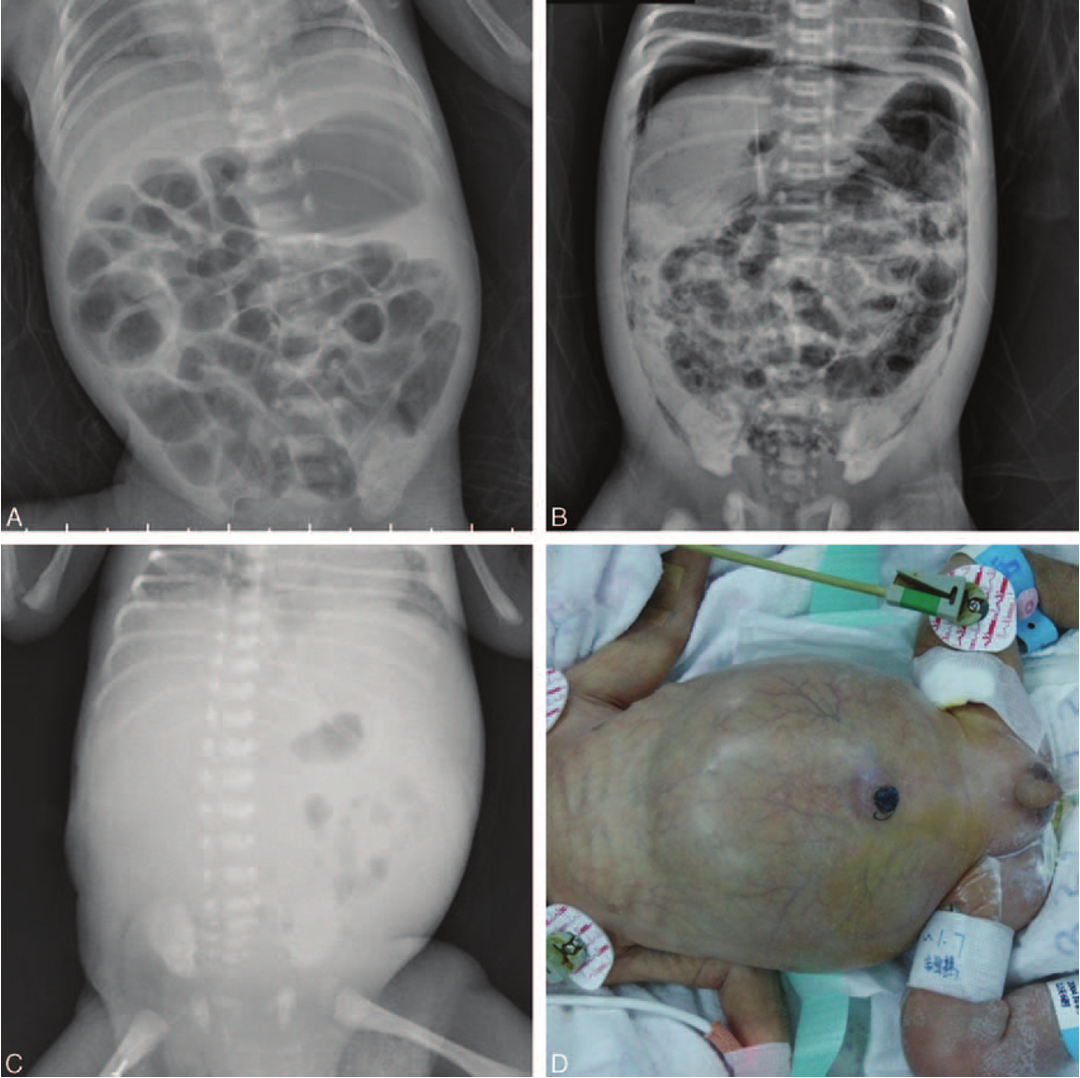

Radiography: Abdominal X-ray:

• Dilated loops,

• thickened bowel walls,

• pneumatosis intestinalis (air in intestinal walls),

• pneumoperitoneum; indicate perforation (emergency requiring surgical intervention),

• portal gas (present in the portal venous system,

• considered to be a poor prognostic sign). 3rd abnormal gas patterns 4th cellulitis/perforation

• Cellulitis of the abdominal wall